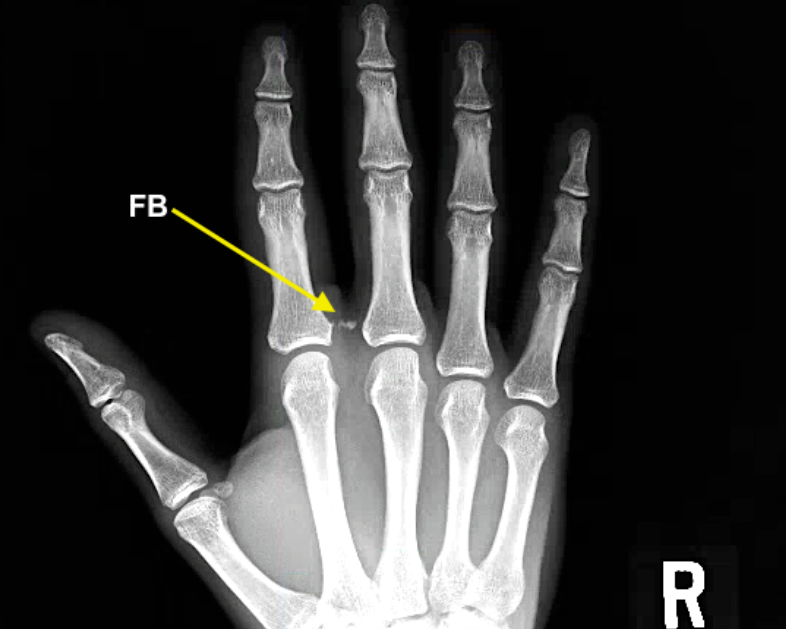

단순 X-ray로 금속, 유리 등 고밀도 이물질은 대부분 확인 가능하며, 나무나 식물성 이물질은 명확히 드러나지 않을 수 있으므로 초음파 검사나 CT가 유용합니다.

비교적 큰 덩어리의 유리 파편

쇠조각

CT소견상 정확한 위치등을 파악하기 좋음